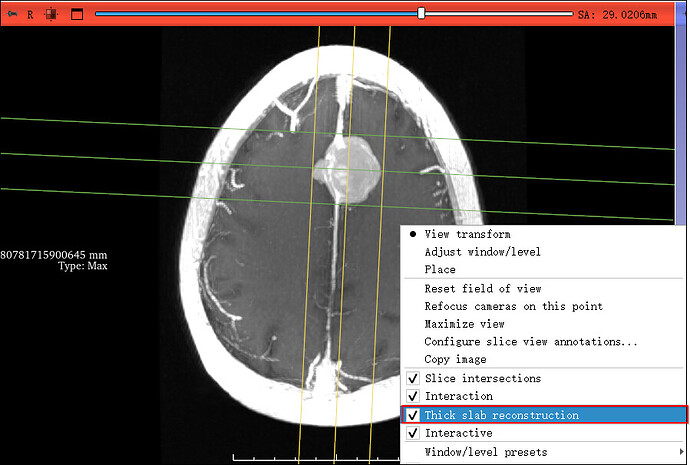

在 2D 视图(红/绿/黄)中,右键单击图像区域;

在弹出菜单中勾选

Thick Slab Reconstruction;

建议同时勾选

Interactive (实时更新模式)。

启用后,图像左上角会出现 “Thickness: × mm Type: Max” 提示,表示厚度与投影类型已生效。